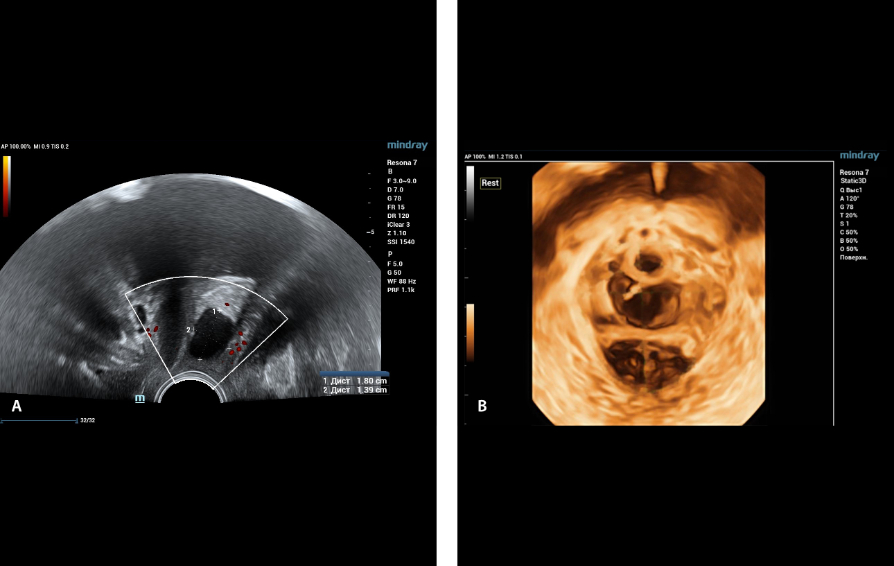

?? ?? ??? ?????(Endocavity volume convex array transducer)(DE10-3WU, Resona 7, ?????)? ??? ??? ???, ??? ?? 1/3 ?? ? ??(anterior vaginal wall)? ???? 18x14 mm ??? ?? ??(an ovoid-shaped formation) with a parietal fine suspension, ????? ??? ???? ??(non-displaced), ????,? CDI ??? ?? ?? ???? ????????. 3D ??? -? ??? ? ??(hyperechoic septa)? ?? ???? ??? ?? ??.

?? ??? ?? ???(Volumetric reconstruction)? ??? ??? ?? ??? ?? ??? ??? ? ??? ?? ??????? ??? ??? ??? ???.